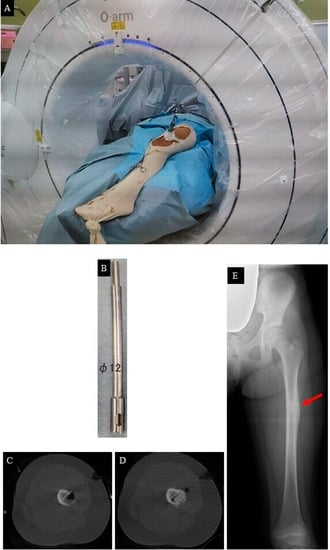

2. Case Presentation

- Tumor resection and femoral stabilization, according to results of FEA.